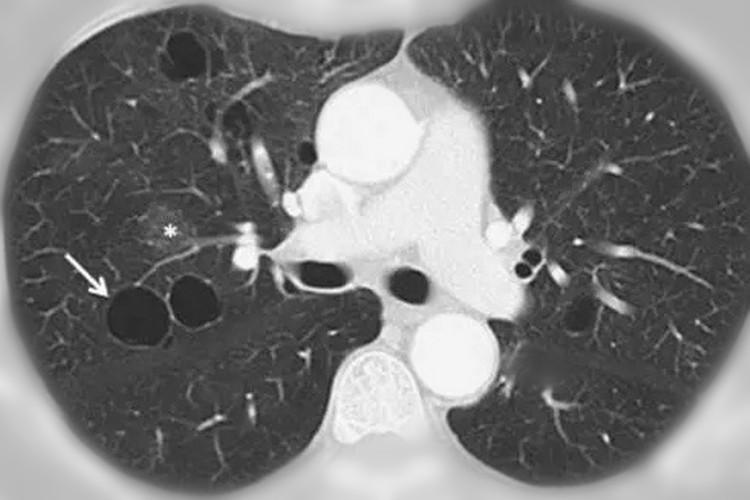

肺大泡,肺气肿,肺气囊,囊肿,空洞,ct如何鉴别?

如何区分"肺大疱","肺气囊","肺囊肿"

你报错了多少"肺气囊"?

肺气肿,肺大泡,肺气囊有什么不一样?